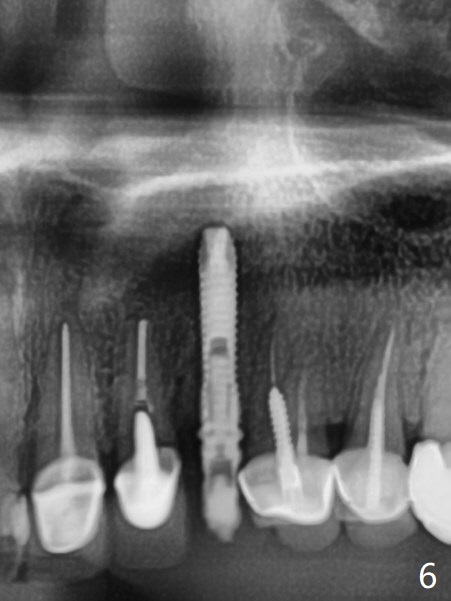

In spite of severe apical infection (Fig1,2 *), a thin narrow strip of the buccal plate (arrowheads, corresponding to the keratinized gingiva) is present when the tooth #11 is extracted. The thin bone keeps the bulging alveolus, i.e., reservoir for bone graft (Vanilla/Osteogen Fig.4 *) after placement of a 3.8x16 mm implant (Fig.3,4). A 4.5x1 mm temporary abutment, placed and trimmed for an immediate provisional, seems to be short in cuff. When an implant is placed deep to prevent periimplantitis, the cuff should be longer, i.e., 3 mm. X-ray should be taken for the depth confirmation after temporary abutment placement. Eight days postop, the mesial gingiva erythema has subsided (Fig.5 < (P: provisional)), while the apical swelling is no longer tender and most likely due to packed bone graft (*). Panoramic X-ray taken 2 weeks postop shows the clearance from the nasal cavity or the maxillary sinus (Fig.6). While the hard tissue around the implant seems to be healthy 5 months postop (Fig.7), the soft tissue is not (Fig.8). The temporary abutment is changed to a cemented one (4.5x5(2) mm) for impression (Fig.8). Since the neighboring crowns are PFM (Fig.6), the new crown will be made of the same material for shade match. Indeed PFM helps shade match in this case as well (Fig.9,10). Switching abutments (from temporary to cemented) makes it difficult to seat the crown. Post cementation X-ray leaves record for future contact loosening. The buccal gingiva remains erythematous associated with open margin (Fig.11 >) 1 year 4 months post cementation. There is no obvious bone loss 1 year 4 months post cementation (Fig.12). It appears that the crown and abutment need to be changed. Although the gingival margin remains erythematous, the gingival hemorrhage is basically lacking due to better oral hygiene during Shelter at Home (1 year 9 months post cementation, Fig.13). Change in abutment and crown will be conducted post coronavirus pandemic. In fact the abutment is incompletely seated (Fig.14 <). In addition, the tooth #12 is symptomatic with PARL associated with the buccal root (*). CBCT indicates possible buccal root fracture (Fig.15,16 ^) and loss of the buccal plate (Fig.16 <).